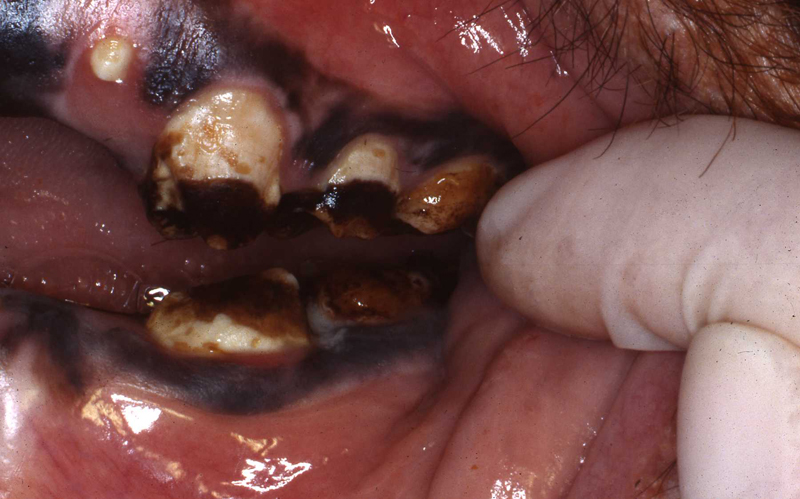

Periodontal Disease

The next most common pathosis encountered is periodontal disease. Again, improvement in diets has reduced this disease. I strongly believe that besides nutrients, diet texture is very important in optimizing oral health, minimizing periodontal disease. I believe that soft or pelleted foods that do not stimulate and challenge the dentition and periodontium may contribute to periodontal disease. Duplicating natural diets in this manner for diverse species is of course, not always possible, but zoos do make efforts to do so when they can.

In the gorillas and bonobos that were born and raised here at Milwaukee County Zoo, we have not had many periodontal problems. We have had adult gorillas come to us from other zoos with significant periodontal disease.

Most or our orangutans however, have had chronic, serious periodontal disease. All of our males have eventually lost all their teeth due to periodontal disease. That has not been the case with the females. We are not the only zoo that has had the chronic periodontal problems with orangutans. See Dr. Norm Stollers' paper: In the typical orangutan case that I have dealt with, there is not much accumulation of plaque or calculus. However, deep periodontal pocketing and bone loss progresses until the teeth become very mobile. I have not observed much bleeding in the most severe of these cases. We discussed preventive strategies and even tried chlorhexidine gluconate rinses to subdue the disease process. However, the orangs did not accept the products, probably due to the taste.